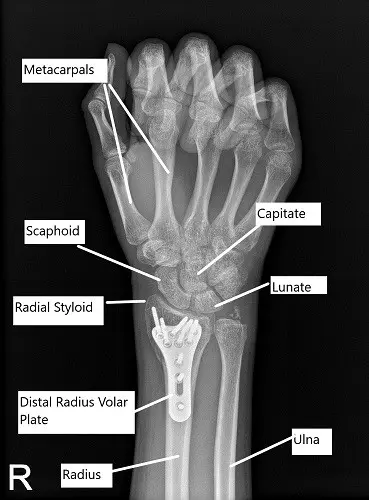

Post-operative x-ray of the right wrist in PA view.

Finding the fracture and the plate in an acceptable position, the distal fragment was fixed using locking screws including two radial styloid screws. The first screw was a cortical screw to pull the plate to the bone. The cortical screw was wasted at the end of the procedure. The proximal fragment was fixed using a combination of locking and non-locking screws. The final fixation of the plate was checked in AP and lateral views and found to be satisfactory.

Transfixation of the radioulnar joint was performed using K-wires. The final pictures were taken in AP and lateral views and saved. The wound was thoroughly washed and closed in layers using #2-0 Vicryl and #4-0 Monocryl. Dermabond was used for the skin. The dressing was performed using 4 x 4s, Xeroform, Webril, posterior long arm splint, and Ace wrap. The patient was moved to Recovery in a stable condition.